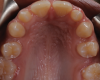

A 16-year-old female patient presented with the chief complaint that she was dissatisfied with the appearance of her anomalous maxillary lateral incisors (teeth Nos. 7 and 10) and multiple diastemas (Figure 1 through Figure 4). She had been referred for restorative treatment after an initial consultation with the orthodontist. Her first restorative appointment was dedicated to data collection, which included a health history and physical examination as well as the acquisition of photographs (facial, dentofacial, dental), videos (chief complaint, F sound, S sound), vinyl polysiloxane (VPS) impressions, a panoramic radiograph, a bite registration, and a facebow registration. The clinical examination revealed that both of the patient's maxillary lateral incisors were peg-shaped. After a discussion about the risks and benefits of different treatment options, such as direct composite restoration, indirect composite veneers, and porcelain laminate veneers, she chose to have her maxillary lateral incisors treated with direct composite buildup restorations. The index cutback technique was chosen for this case instead of a freehand technique in order to create a new shape according to an ideal wax-up but also to be able to control the thickness of the enamel layer.7